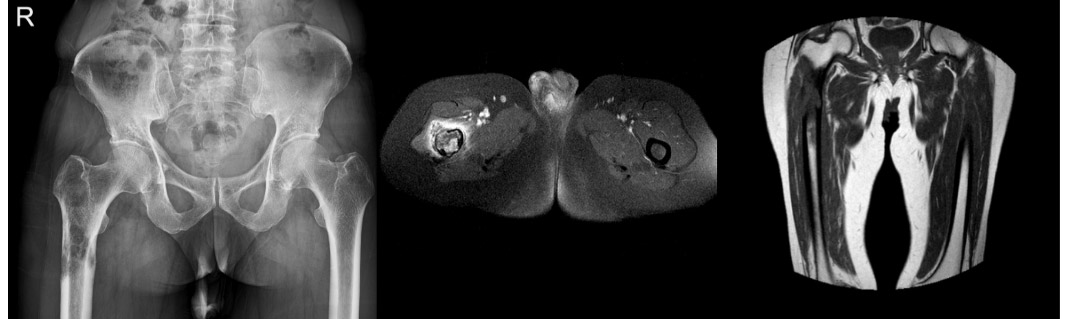

CASE 31: Thyroid cancer increases the risk of fracture in the right thigh (femur) bone due to metastasis.

Before the surgery: X-ray shows lytic lesions in the right proximal femur. MRI reveals severe destruction of the bone cortex, tumor extension beyond the bone, and widespread edema.